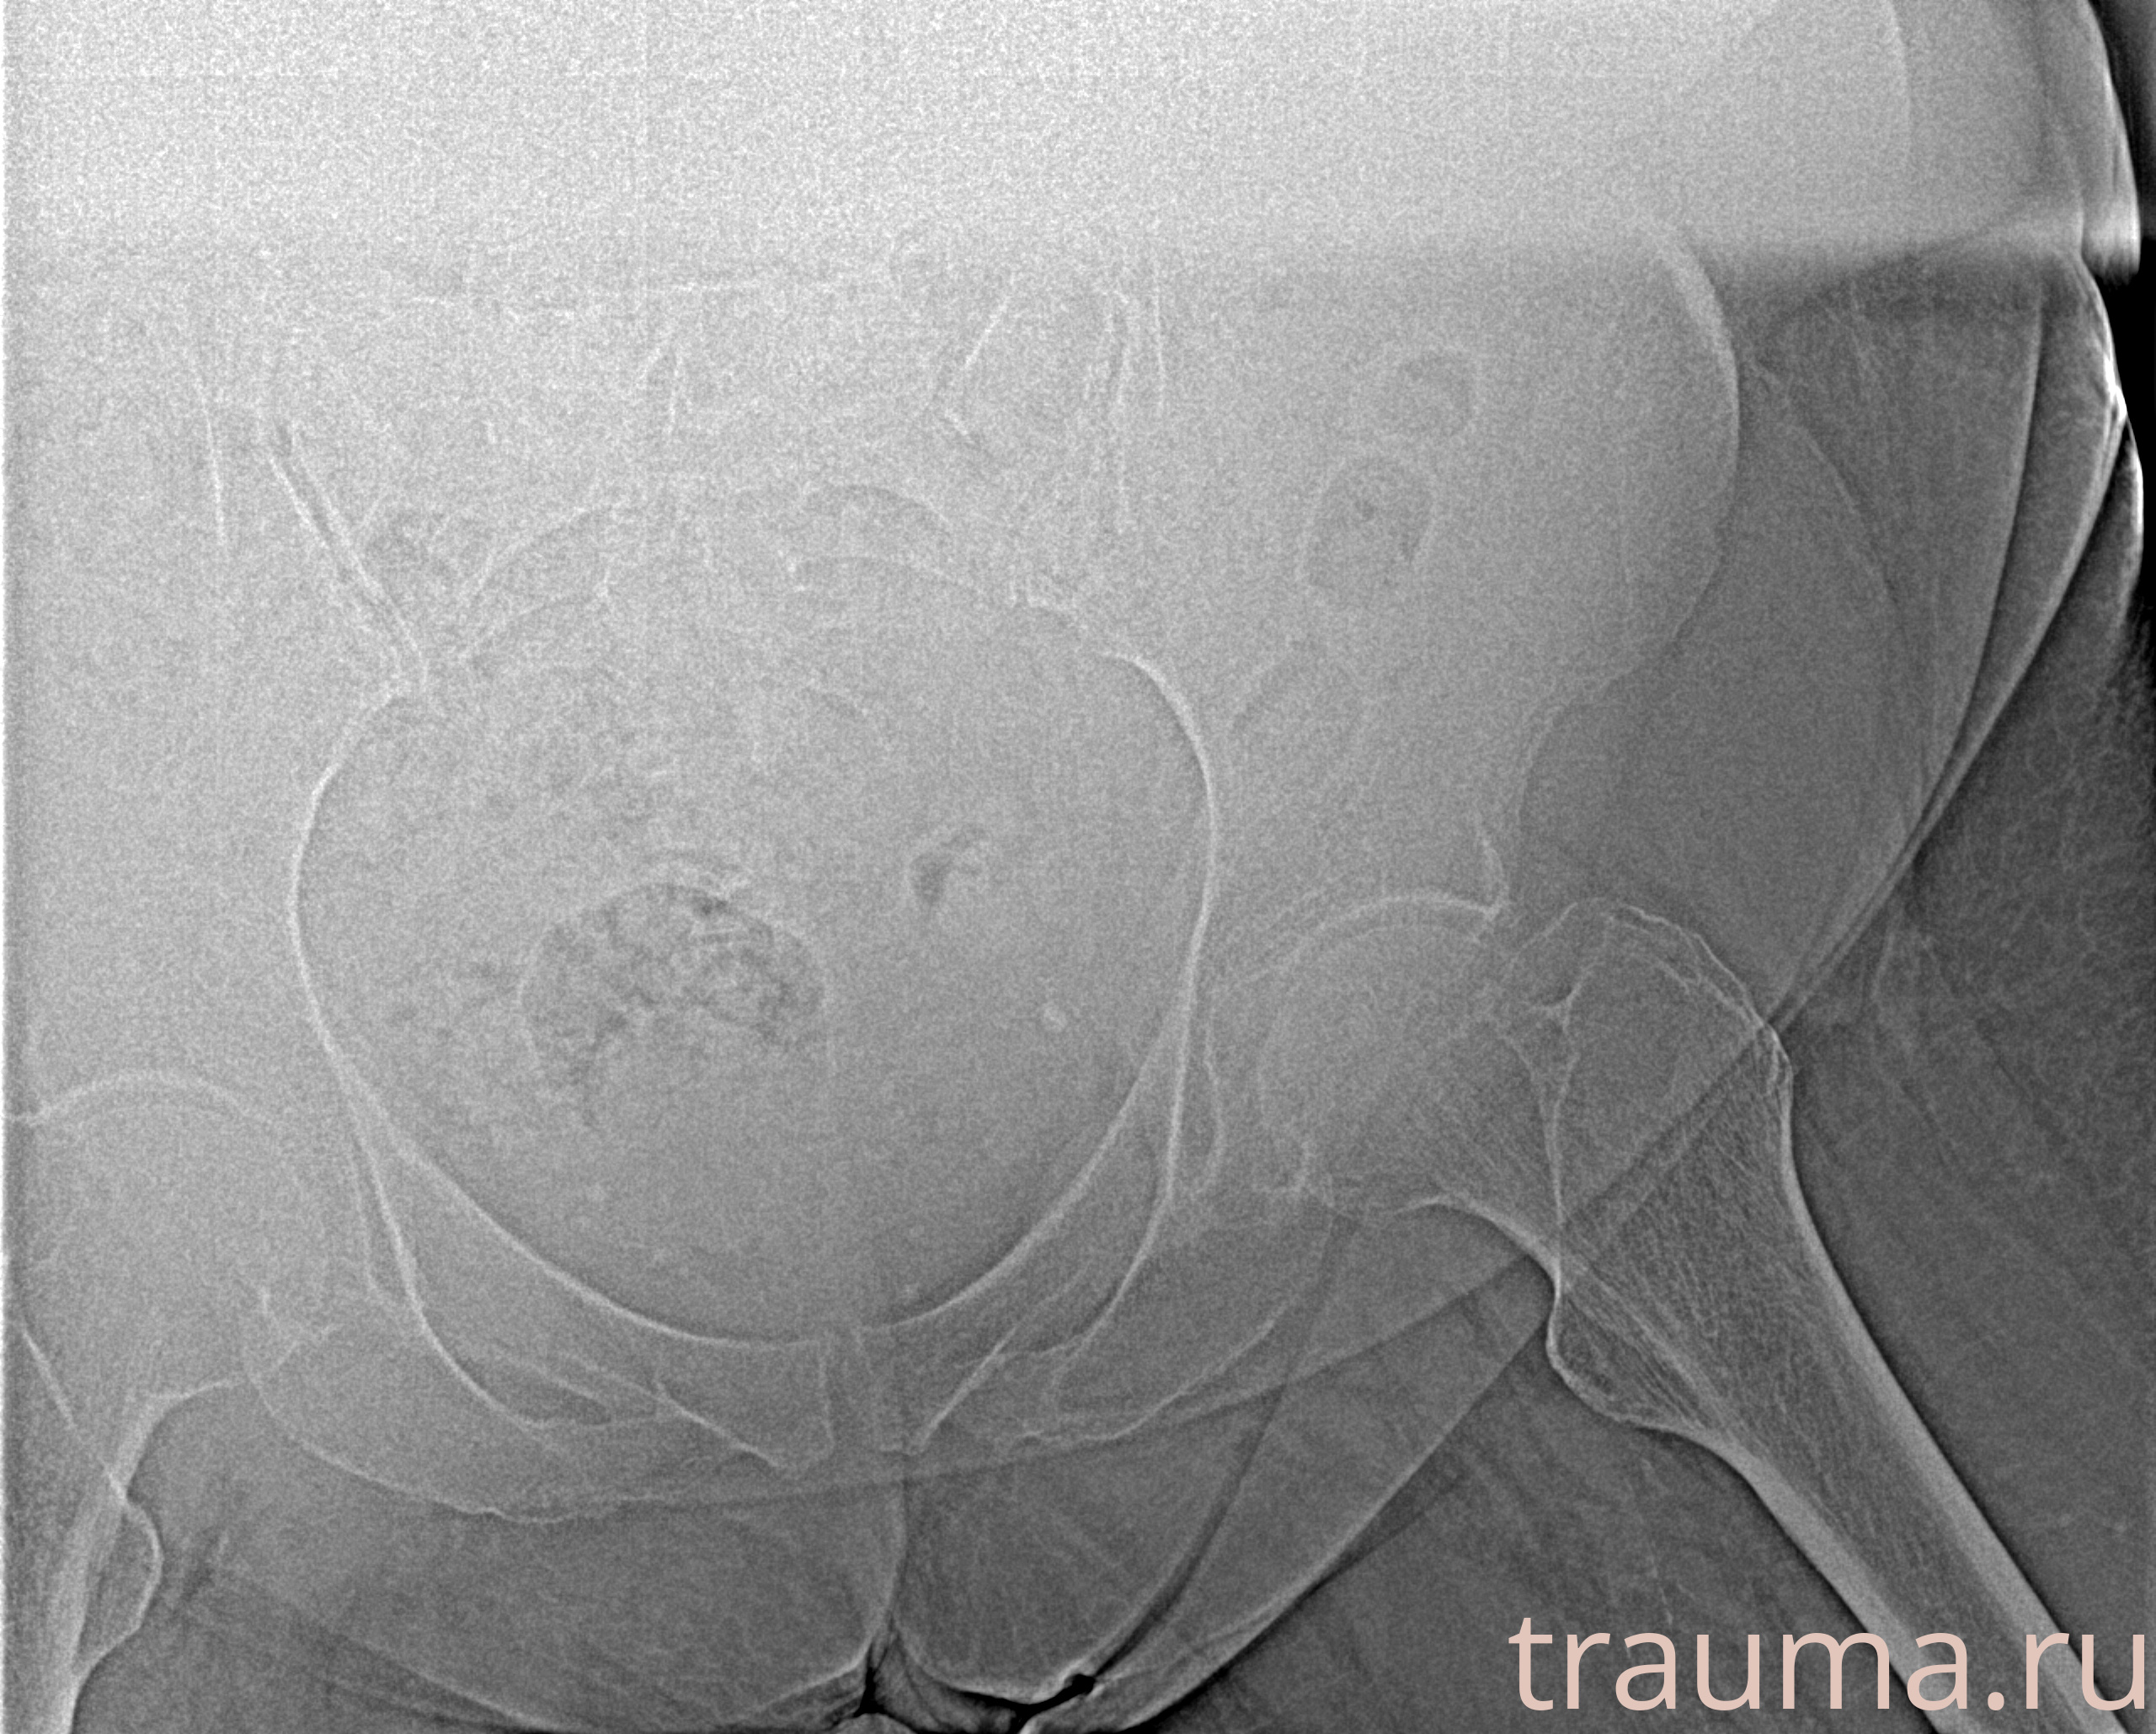

Рентгенограммы

Рентген на дому: по вашему адресу приезжает врач-рентгенолог, травматолог-ортопед с мобильным рентгеновским аппаратом, проводит диагностику травмы или заболевания, делает необходимые рентгенограммы, дает рекомендации по дальнейшему лечению. Получить качественные снимки в домашних условиях возможно благодаря уникальной методике, разработанной МосРентген Центром для института  Склифосовского